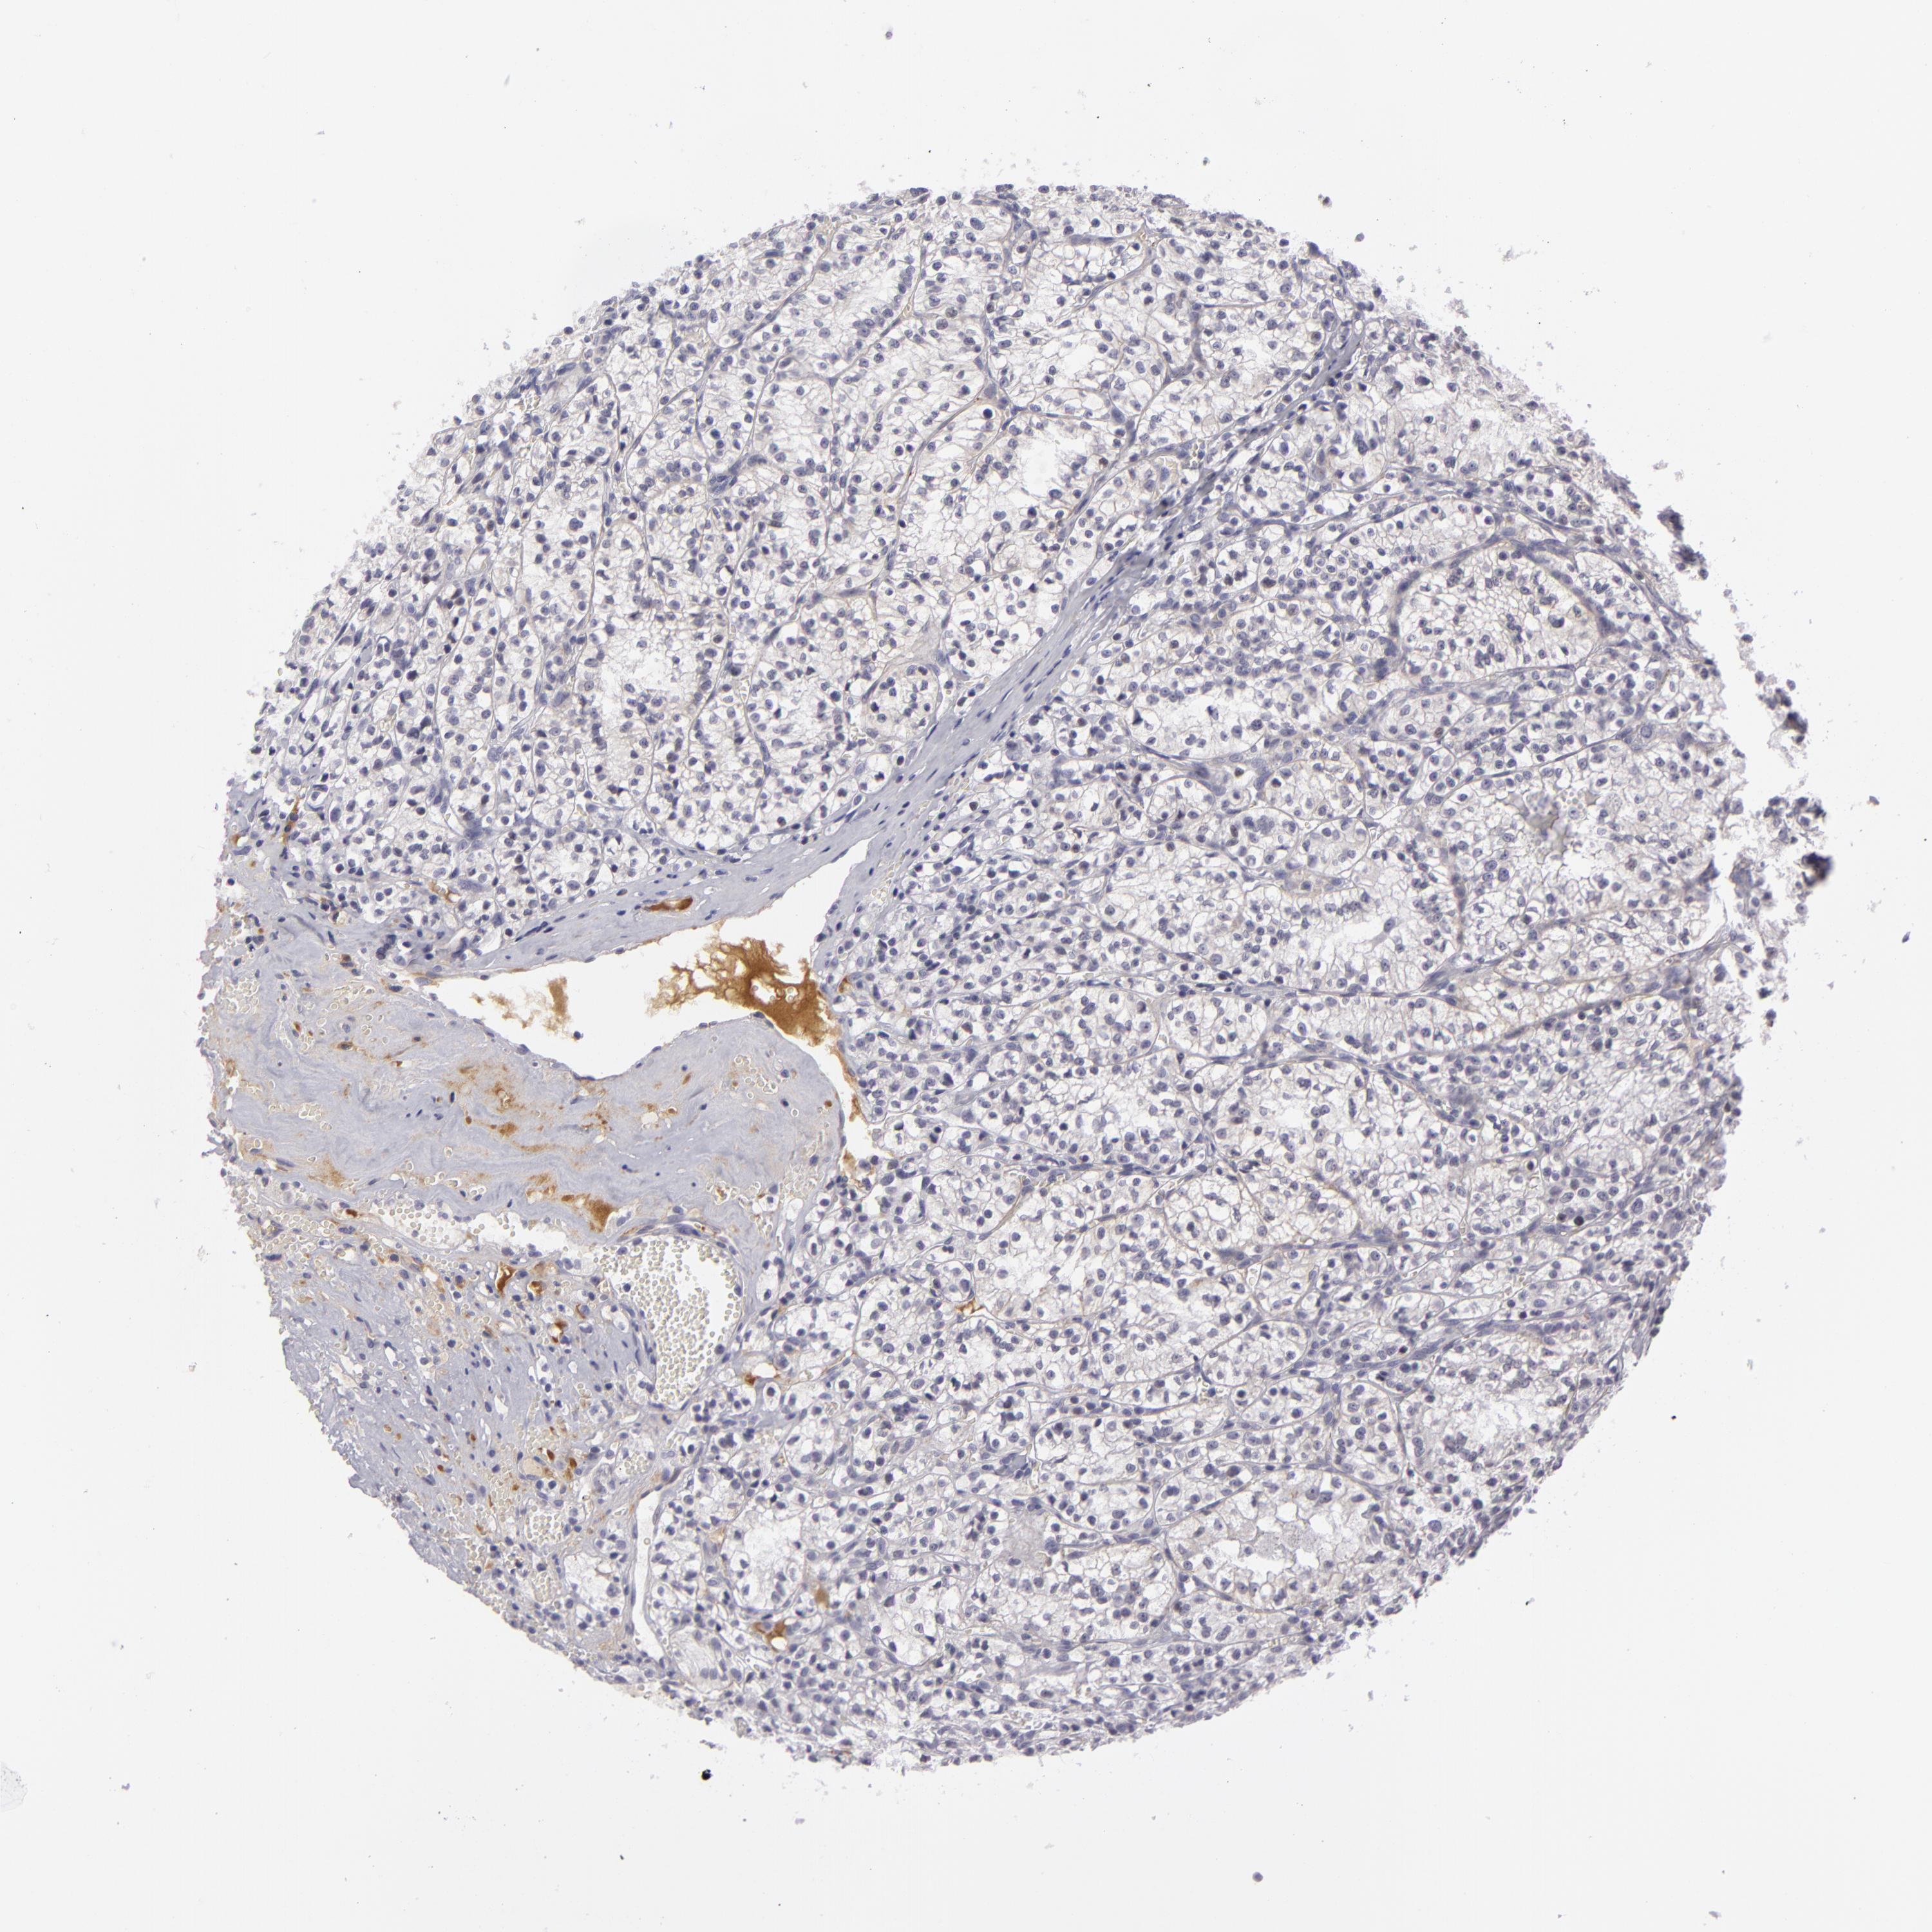

CANCER RENAL CANCER Show tissue menu

KICH TCGA KIRC TCGA KIRC VALIDATION KIRP TCGA PROTEIN RCC CPTAC PROTEIN EXPRESSION